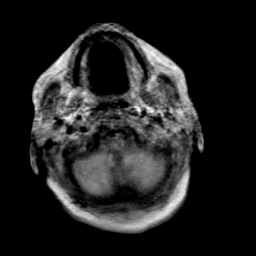

Creutzfeld-Jakob disease: proton density-weighted MR -- Slice #1

[Home][Help][Clinical] Slice 1